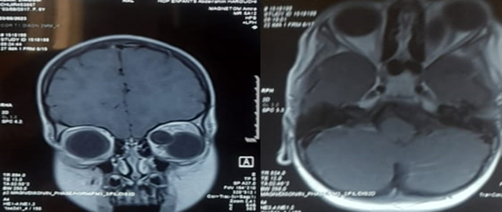

Orbital CT and MRI were performed

CT imaging revealed a well-defined mass, approximately 3 cm in size, enhanced by contrast, causing grade III exophthalmos without globe invasion or evidence of bone erosion. MRI showed a well-demarcated left intraorbital lesion, hypointense on T1-weighted images and hyperintense on T2-weighted images, suggestive of a benign hydatid cyst. The patient underwent surgical excision of the lesion. Histopathological analysis confirmed the diagnosis of a hydatid cyst. Postoperative clinical evolution of the left eye was marked by a gradual resolution of inflammatory signs and regression of the exophthalmos.

Figure 4: Axial and coronal section of facial CT scan showing the orbital cyst